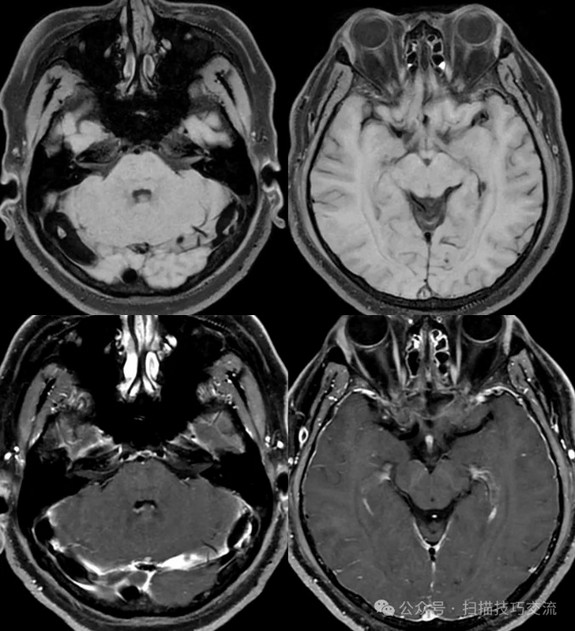

•汗腺分泌:正常,皮肤划痕正常反应。 •尿便障碍:无。性功能障碍无。 •专科情况:正常。不逐一罗列。 •辅助检查:01-05颅脑CT提示:1,上矢状窦、双侧横窦密度较高,请结合临床,必要时进一步检查;2,双侧脑室后角可疑稍高密度影,右顶叶局部脑沟密度可疑增高,建议进一步检查。 •初步诊断:静脉窦血栓

临床申请:颅脑平扫,静脉成像,磁敏感成像,颅内静脉血管黑血成像。

SWAN未见异常。